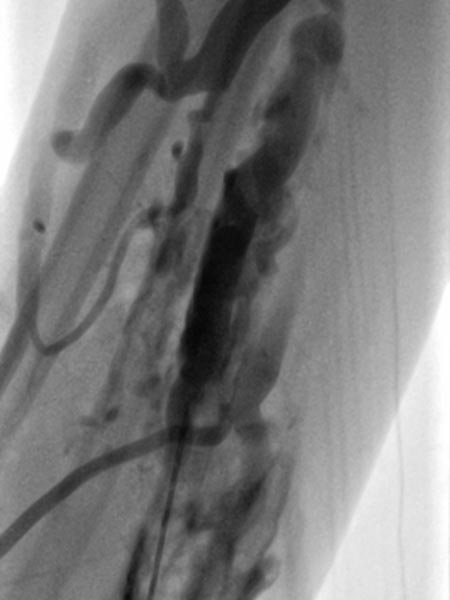

Entsprechend der relativ kleinen einzelnen Gefäßdurchmesser der venösen Malformation ist diese auch nur schwer direkt zu punktieren. Die Varikographie in Direktpunktionstechnik zeigt multiple, eher längliche, zum Teil netzartige dysplastische kleinlumige Venenkanäle.

Nach Sicherung der Nadellage innerhalb der venösen Malformation und Ausschluss eines Abstroms über eine größere Kommunikationsvenen, wird Polidocanolschaum (3% Äthoxysklerol 1 zu 4 in Luft aufgeschäumt) injiziert. Dieser Schaum ist nicht röntgendicht sondern verdrängt das vorher injizierte Kontrastmittel aus der Läsion.